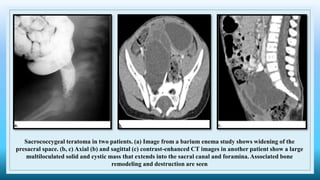

Sacrococcygeal teratoma in two patients. (a) Image from a barium enema study shows widening of the

presacral space. (b, c) Axial (b) and sagittal (c) contrast-enhanced CT images in another patient show a large

multiloculated solid and cystic mass that extends into the sacral canal and foramina. Associated bone

remodeling and destruction are seen